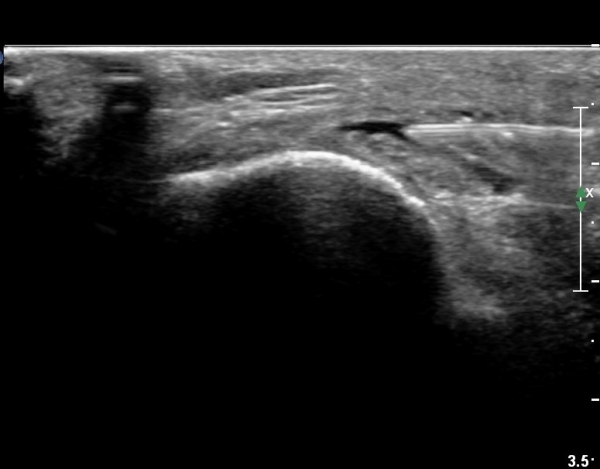

ŽÃËÀÚ¸¦ Á» ´õ ¸»´Ü, ¿ÜÃøÀ¸·Î À̵¿ÇÏ´Ï ºñ°ñµÎ Ç¥Ãþ¿¡¼­ ºñ°ñ½Å°æÀÌ Àú¿¡ÄÚ·Î °üÂûµÈ´Ù(»çÁø 3, 4, 5).